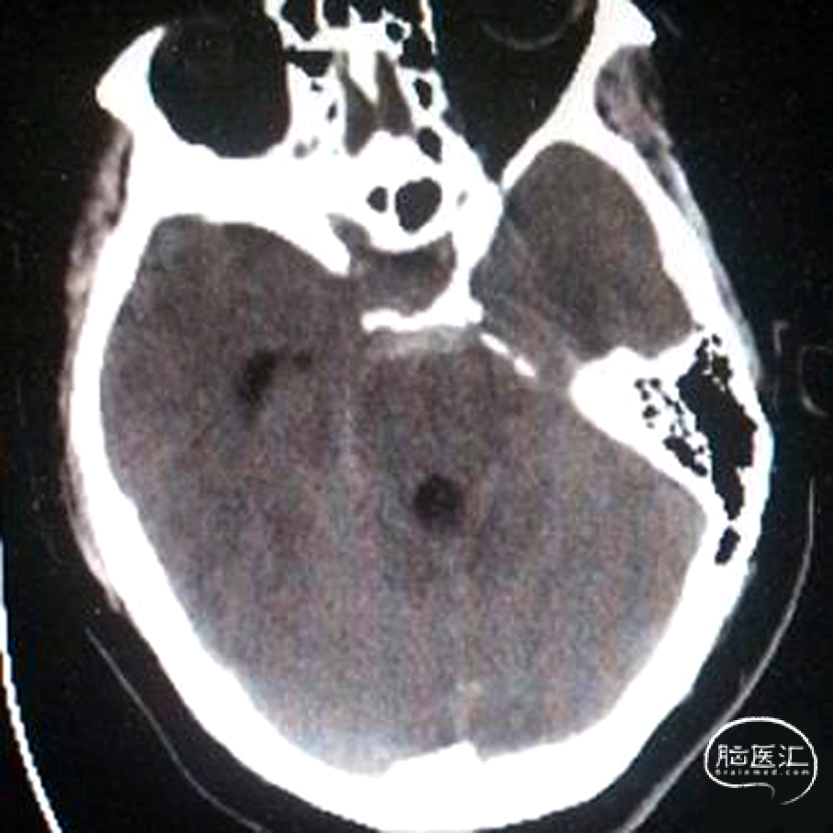

发病当天头颅CT提示蛛网膜下腔出血,出血以环池周边为主,右侧侧脑室后角少量积血

入院急诊DSA提示右侧小脑后下动脉远端动脉瘤,动脉瘤位于PICA蚓部分支